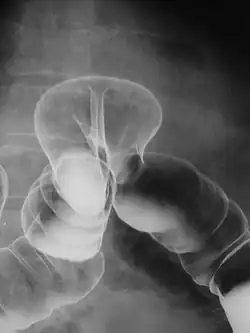

El enema opaco o radiopaco, también llamado colon por enema,o sencillamente "enepaco" es un método de diagnóstico que permite visualizar el interior de la ampolla rectal, sigma, colon descendente, etc. aproximadamente hasta el ángulo de Treitz mediante un enema de un medio de contraste radiopaco (generalmente sulfato de bario, un compuesto químico metálico de color plateado a blanco). A continuación se realiza una radiografía de la zona, en la que, por estar rellena la luz por el contraste, resalta la estructura de la pared interna o revestimiento mucoso del colon.

Cuando se usa bario como medio de contraste combinando con aire para obtener mejores imágenes, se describe como enema con doble contraste. Durante el estudio, se acuesta al paciente sobre la mesa radiográfica y se le coloca el enema con el líquido de contraste.